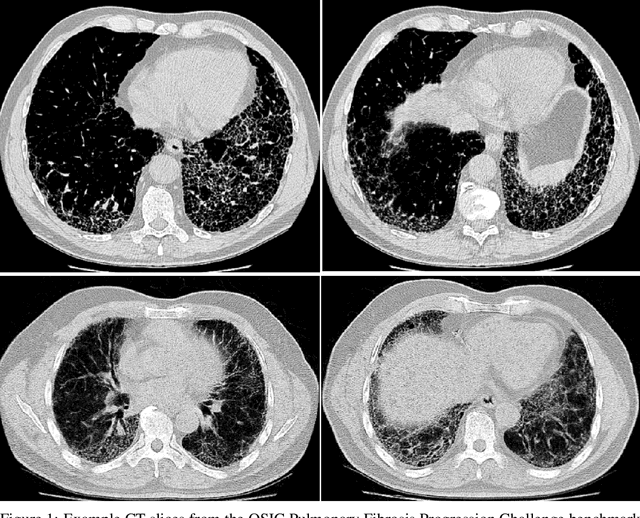

Abstract:Pulmonary fibrosis is a devastating chronic lung disease that causes irreparable lung tissue scarring and damage, resulting in progressive loss in lung capacity and has no known cure. A critical step in the treatment and management of pulmonary fibrosis is the assessment of lung function decline, with computed tomography (CT) imaging being a particularly effective method for determining the extent of lung damage caused by pulmonary fibrosis. Motivated by this, we introduce Fibrosis-Net, a deep convolutional neural network design tailored for the prediction of pulmonary fibrosis progression from chest CT images. More specifically, machine-driven design exploration was leveraged to determine a strong architectural design for CT lung analysis, upon which we build a customized network design tailored for predicting forced vital capacity (FVC) based on a patient's CT scan, initial spirometry measurement, and clinical metadata. Finally, we leverage an explainability-driven performance validation strategy to study the decision-making behaviour of Fibrosis-Net as to verify that predictions are based on relevant visual indicators in CT images. Experiments using the OSIC Pulmonary Fibrosis Progression Challenge benchmark dataset showed that the proposed Fibrosis-Net is able to achieve a significantly higher modified Laplace Log Likelihood score than the winning solutions on the challenge leaderboard. Furthermore, explainability-driven performance validation demonstrated that the proposed Fibrosis-Net exhibits correct decision-making behaviour by leveraging clinically-relevant visual indicators in CT images when making predictions on pulmonary fibrosis progress. While Fibrosis-Net is not yet a production-ready clinical assessment solution, we hope that releasing the model in open source manner will encourage researchers, clinicians, and citizen data scientists alike to leverage and build upon it.